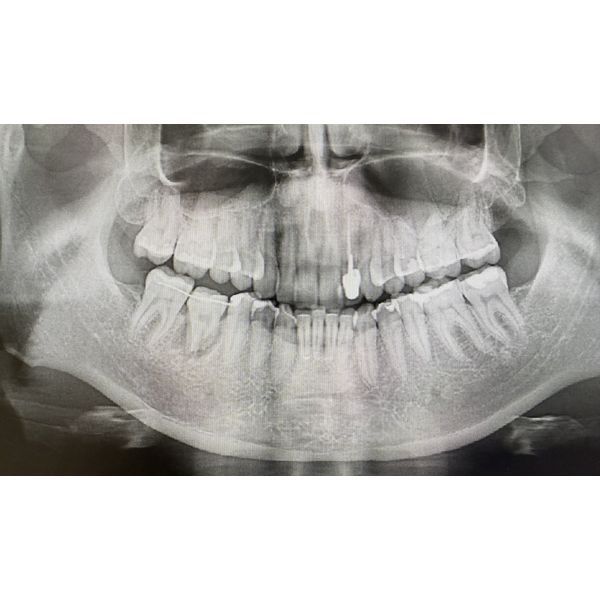

По результатам компьютерной томографии (КТ):

- зуб 4.6: присутствует достаточно выраженная межкорневая костная перегородка толщиной около 5,5 мм, что может служить препятствием для трансплантации зуба, изменений в анатомии костных структур не было;

- зуб 2.8: 4 апекса (вершины корней), каналы зуба широкие, без выраженной кривизны.

- провели контрольную рентгенографию.

КЛКТ показала, что после аутотрансплантации зуб прижился хорошо, костный рисунок восстановился, процесс резорбции (рассасывания) корня не развился.